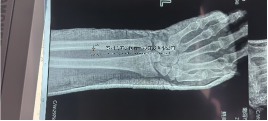

本病例腕架骨折。術(shù)前正側(cè)位片:右橈骨遠(yuǎn)端骨折。